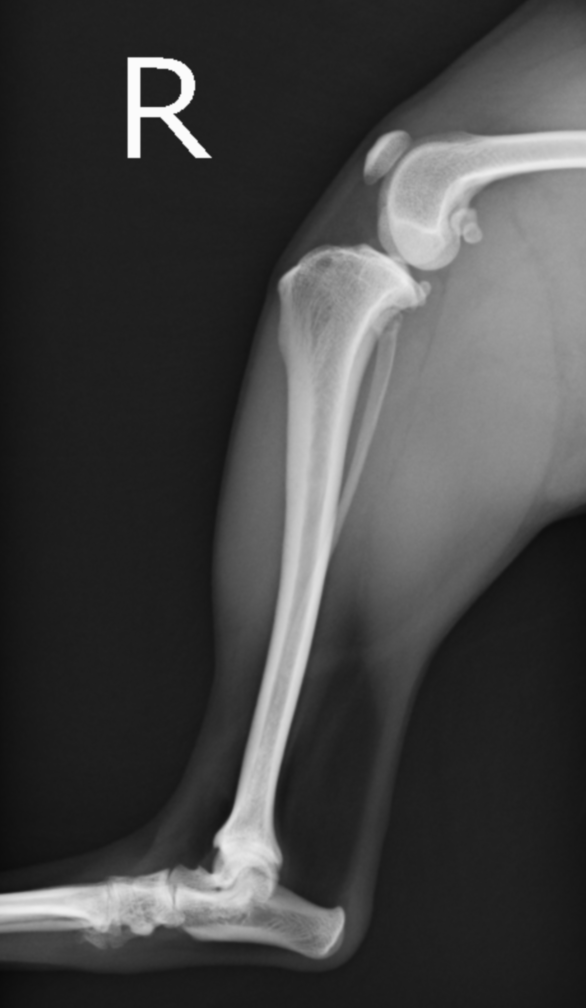

正常肢。大腿骨と脛骨の位置関係が前十字靭帯損傷時と異なり、しっかり連絡性がある